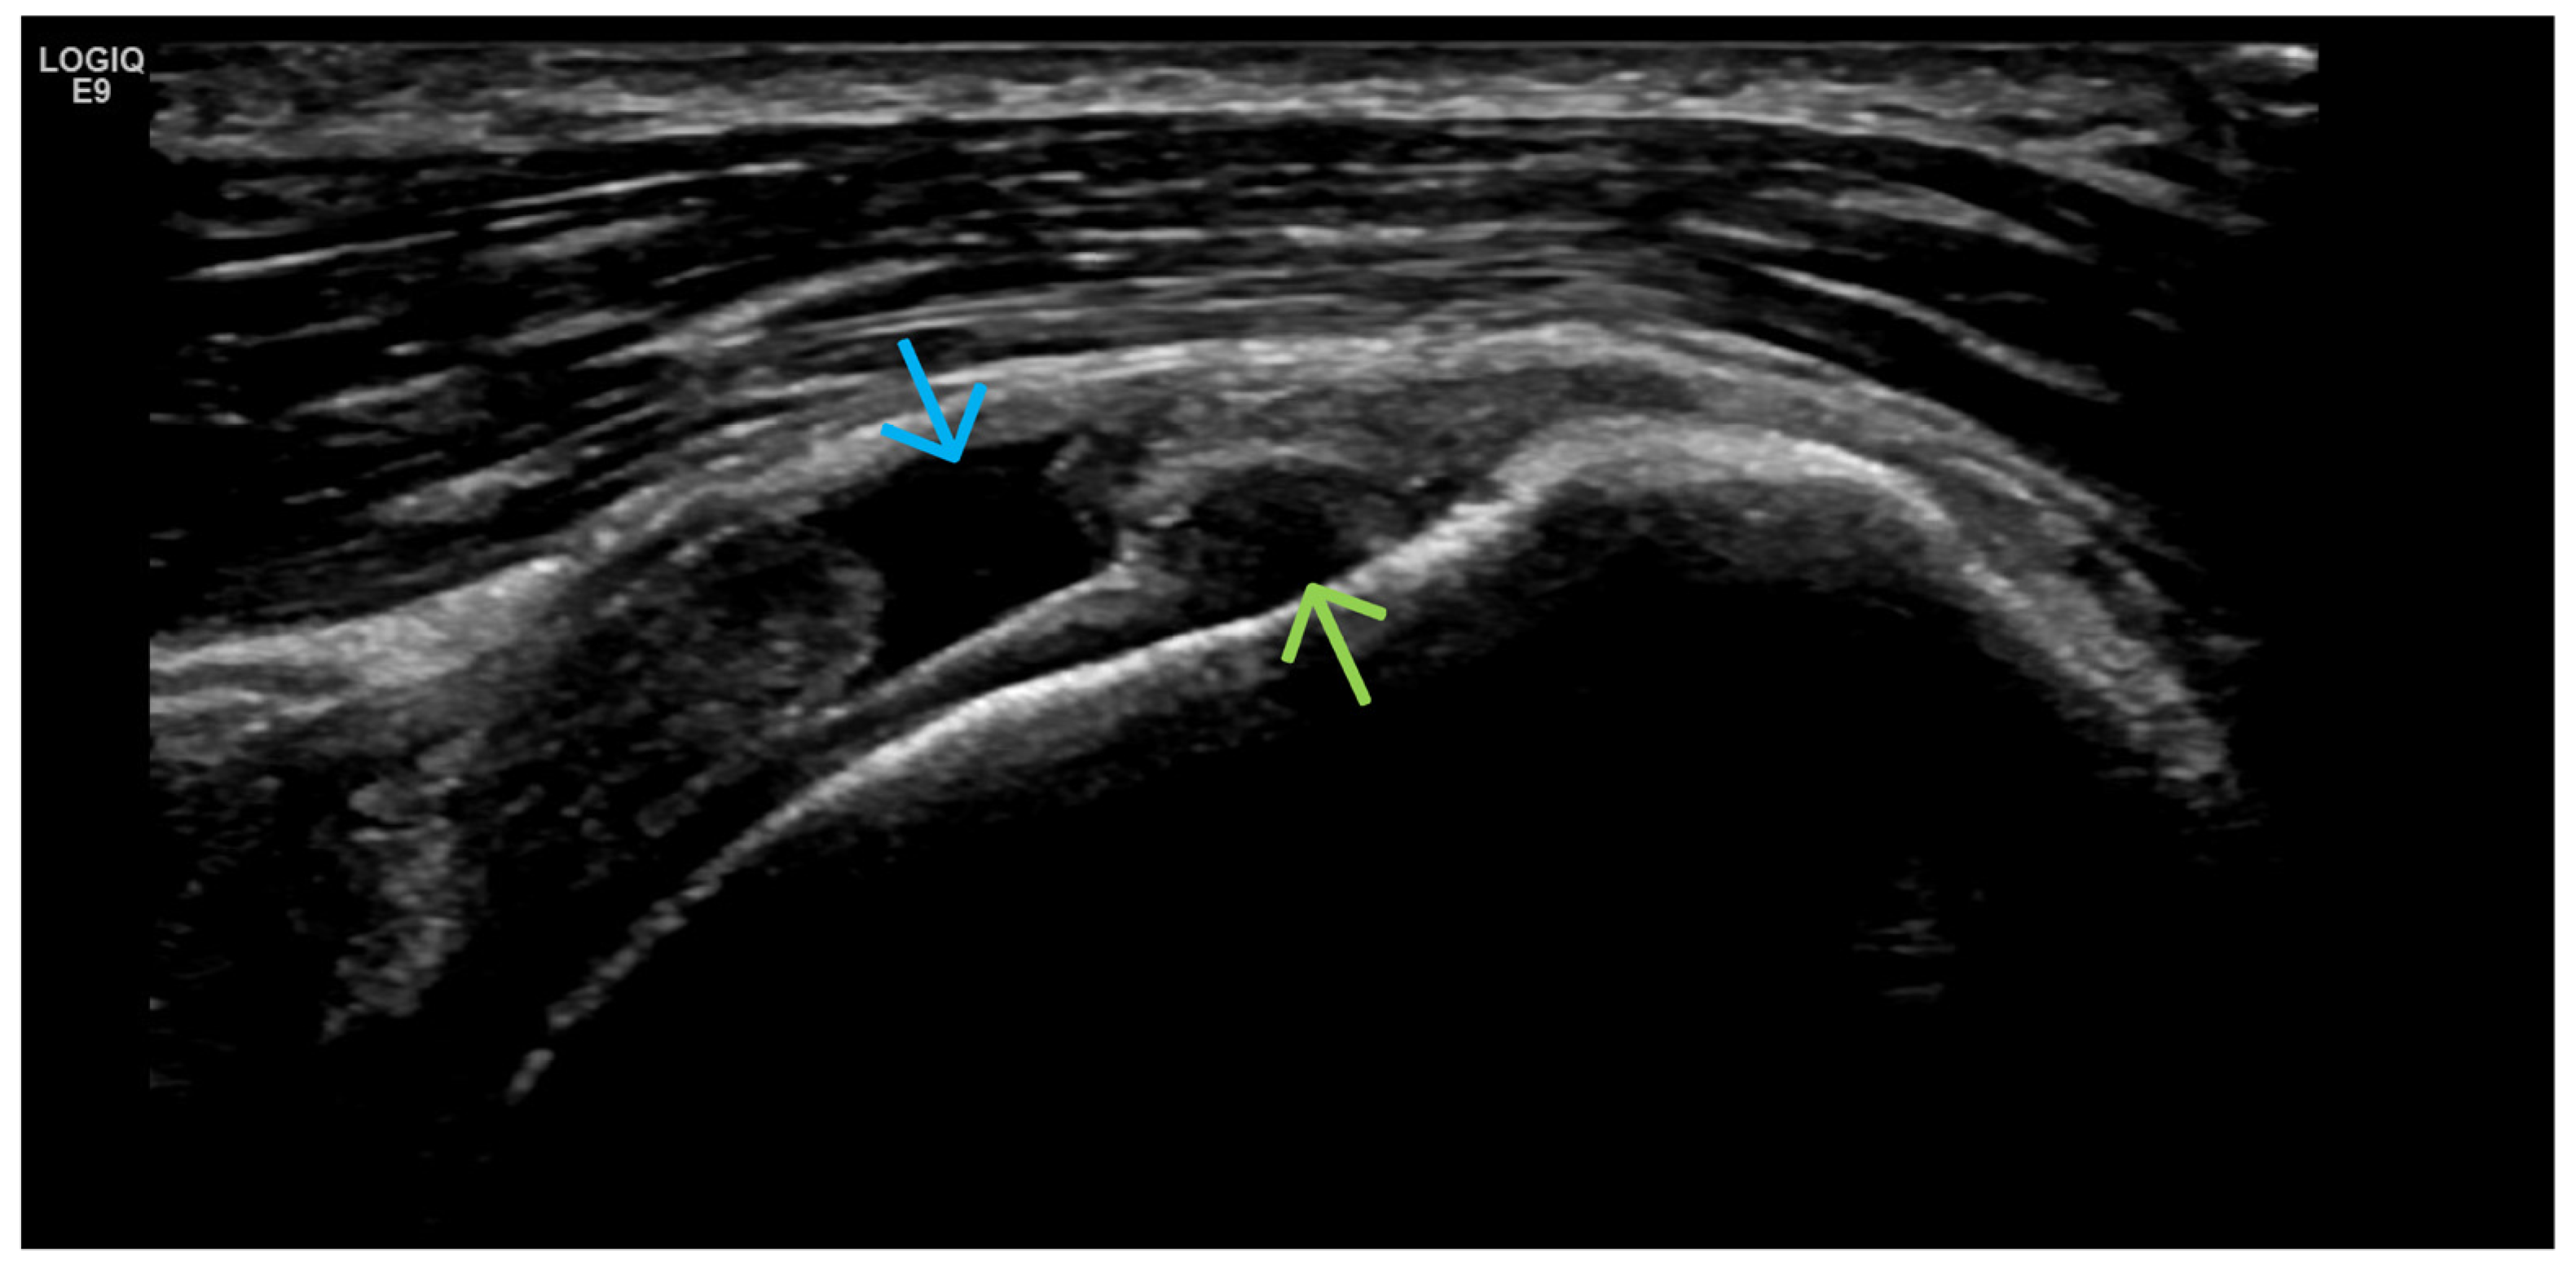

4. Examples of US Phenotypes